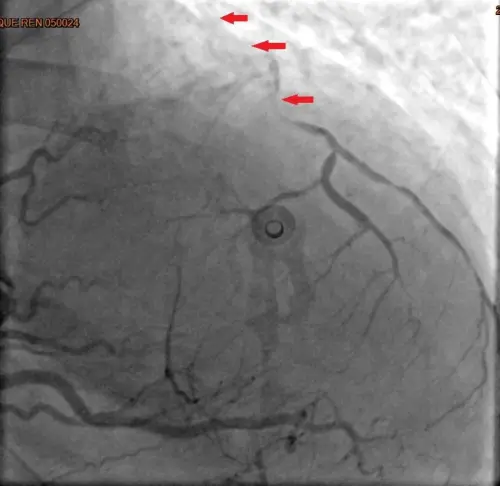

▲林小姐的心導管顯示3條冠狀動脈嚴重阻塞。(圖/台北慈願提供) 宋鎮宇指出,心肌梗塞往年多見於高齡族群,近年因生活作息不規律和飲食習慣改變,發病年齡逐漸下降;根據美國心臟醫學會統計,65歲以上冠狀動脈疾病盛行率為2成,18~45歲也有1.8%,顯示中壯年同樣不可輕忽。